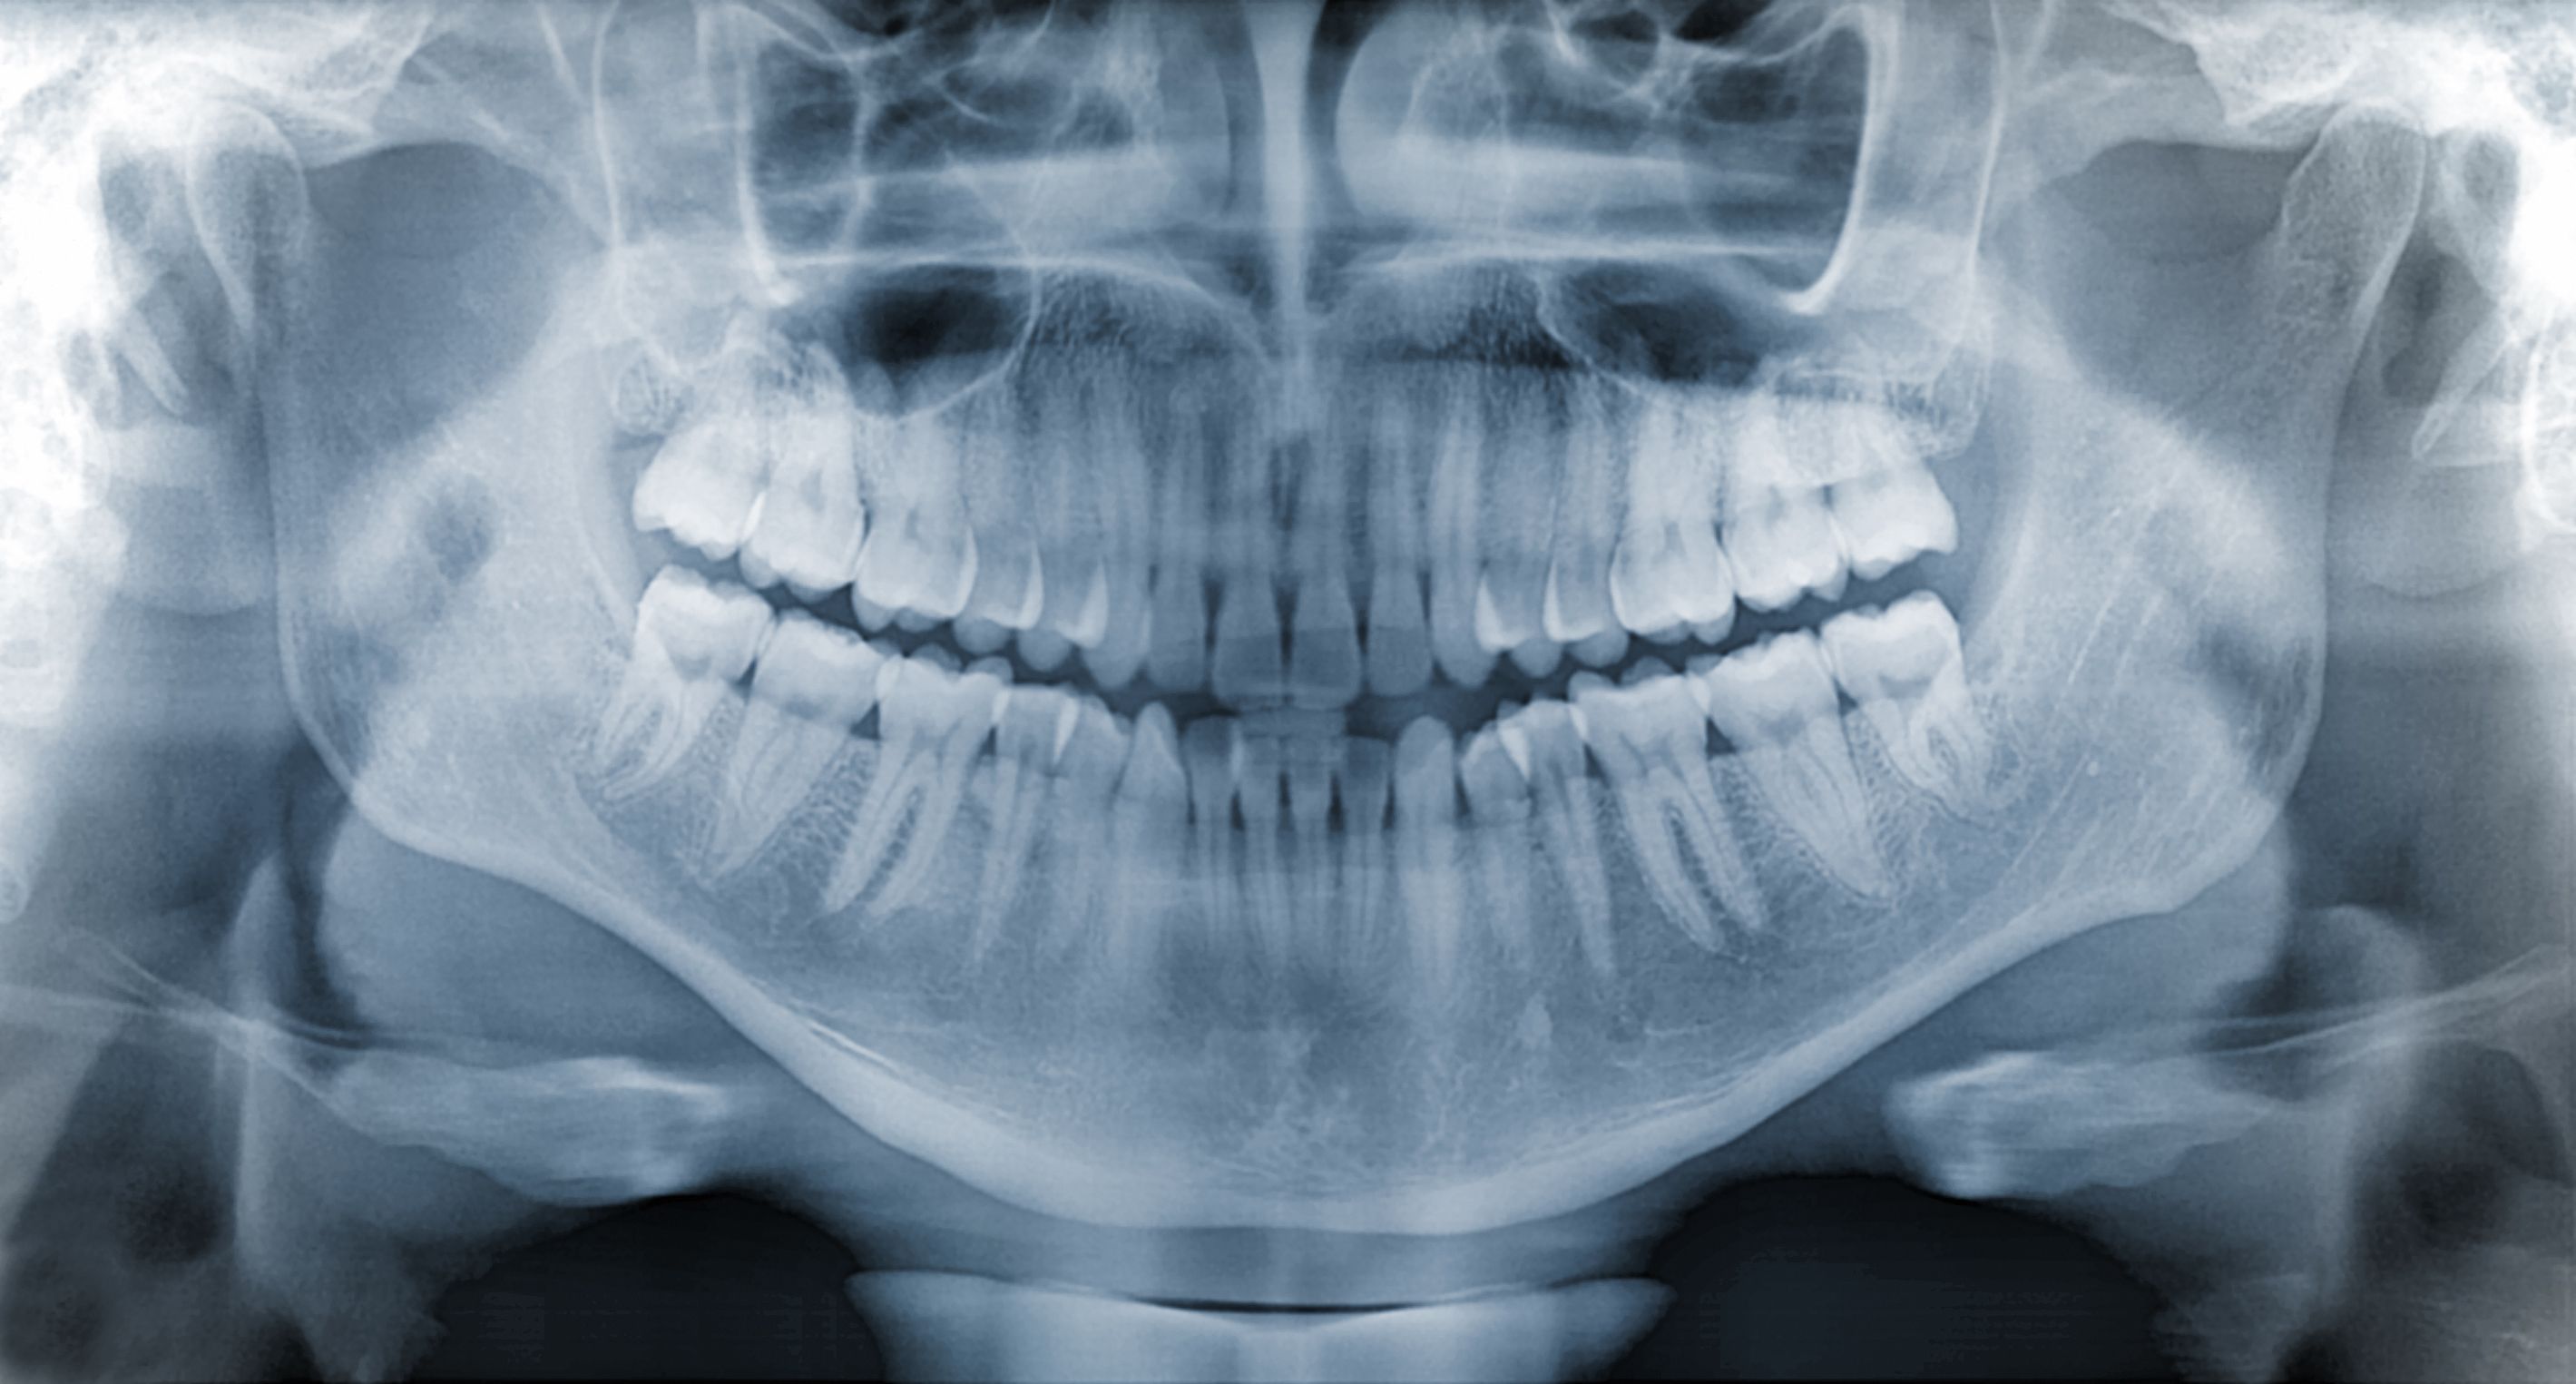

Dental implants are a popular and effective solution for replacing missing teeth. They are designed to provide a strong foundation for fixed or removable replacement teeth that are made to match your natural teeth. However, with several options available, choosing the right dental implant can be overwhelming. This guide will help you understand the different types of dental implants and select the best one for your needs.

Endosteal implants are the most common type of dental implant. They are typically made of titanium and surgically placed into the jawbone. Once the surrounding gum tissue has healed, a second surgery is needed to attach a post to the original implant. Finally, an artificial tooth is attached to the post. Endosteal implants are ideal for patients with a healthy jawbone.

Subperiosteal implants are placed under the gum but on, or above, the jawbone. This type of implant is used for patients who do not have enough healthy jawbone and cannot undergo a bone augmentation procedure. The metal frame is fitted onto the jawbone just below the gum tissue, and as the gums heal, the frame becomes fixed to the jawbone.

Your bone health is a crucial factor in determining the type of dental implant that is best for you. If you have sufficient bone density, endosteal implants are typically recommended. For those with insufficient bone density, subperiosteal implants or bone grafting procedures may be considered.